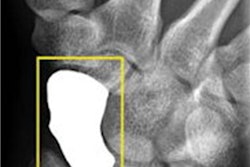

Fracture is the most common condition in the emergency department that leads to a delayed or incorrect diagnosis, and extremity fractures are the second-most frequently missed diagnosis leading to a legal claim, according to the researchers. To see if AI could help avoid undetected fractures, the authors first retrospectively gathered skeletal radiographs from 500 consecutive patients with trauma emergencies. The patients included 232 women and 268 men with a mean age of 37 (range: 0.25 to 99 years old).

Three radiologists -- a senior radiologist with 15 years of musculoskeletal imaging experience, a fellow with two years of musculoskeletal imaging experience, and a third-year resident -- interpreted the radiographs first on their own, and then, one month later, with the help of a commercially available AI algorithm (BoneView, Gleamer). For the purposes of the study, ground truth was determined via consensus reading by the radiologists and AI results.